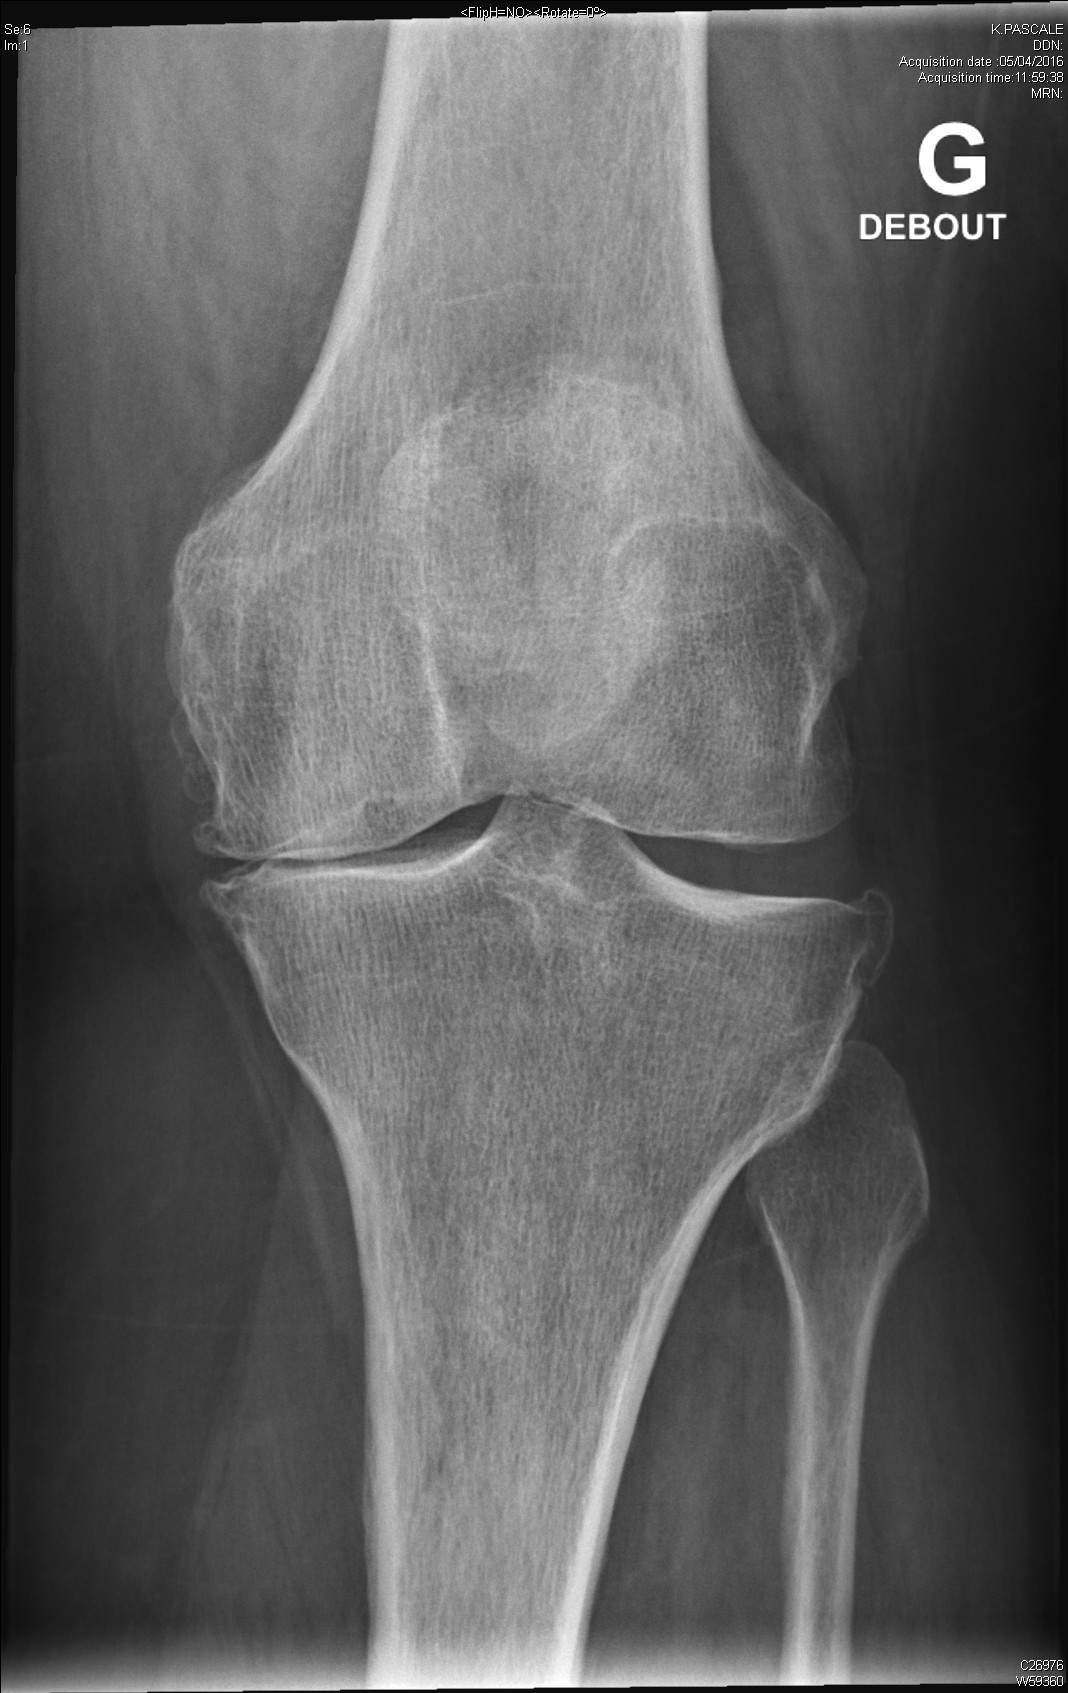

arthrite destructrice évoluée du genou dans le cadre d'une polyarthrite rhumatoïde